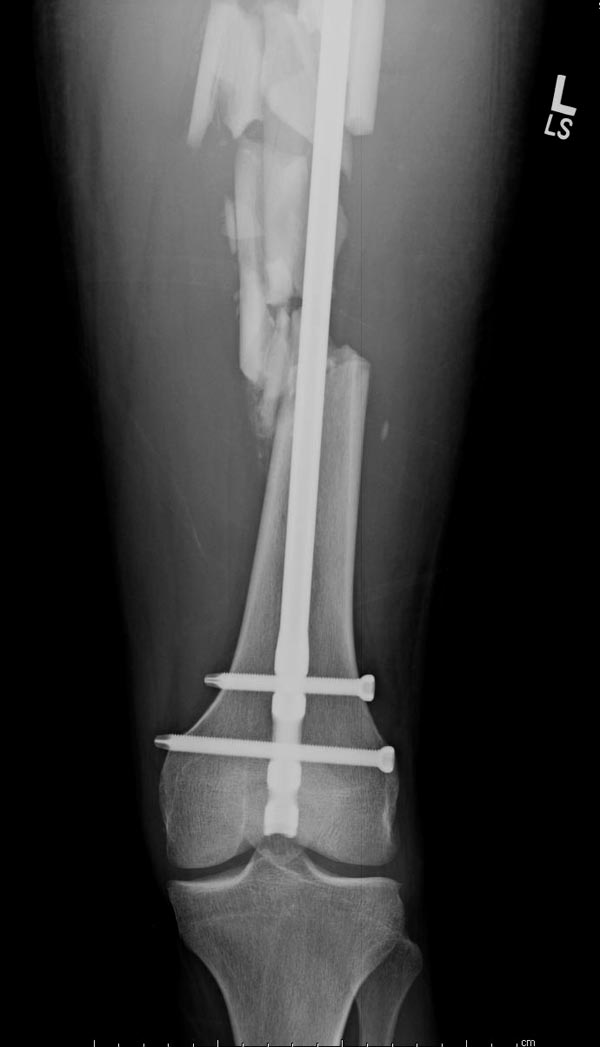

Здесь выставлен ренгенограммы больного, ему 21, травму получил в результате высокоскоростной погони на украденной машине, которая закончилась смертью трех остальных “боевых комрадов”. Начатую коллегой открытую операцию на шейке пришлось закончить мне, установкой винтов и ретроградной фиксацией бедра. Выписка в обычное сроки и наблюдался амбулаторно. Каждый раз напоминали о возможности осложнений ввиде несращения! По истечению 4 месяцев появились признаки варусной деформации. На СТ срезах несращение шейки и бедра. Риминг, замена на более толстый гвоздь и вальгусная остеотомия.

Сразу скажу, что пациент вчера (8.04) прооперирован - артротомия, остеосинтез мыщелков большеберцовой кости канюлированными винтами, открытая репозиция отломков бедренной кости, ретроградный БИОС, остеосинтез надколенника (центральных его отломков) спицами с проволочной петлей. Двухкратная попытка закрытой репозиции шейки на операционном столе после синтеза бедра - абсолютно неэффективна. Учитывая продолжительность и травматичность операции, шейка отложена на 2-й этап. Плечо наверное на 3-й (если вообще делать). Снимки постараюсь предоставить, но чуть позже.